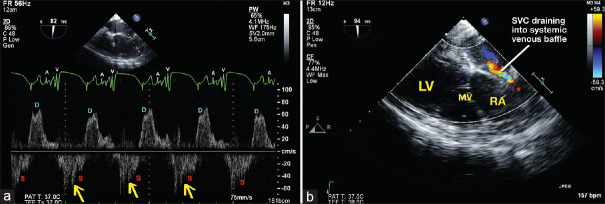

Systolic Flow Reversal Observed in the Superior Vena Cava Doppler Waveform Due to Severe Tricuspid Regurgitation: An Unreported Sign.

严重三尖瓣返流在上腔静脉多普勒波形中观察到的收缩血流逆转:一个未报道的迹象。